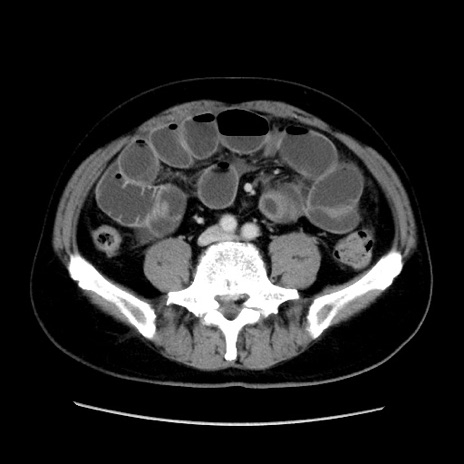

症例16(横断像)

【症例】 70歳代男性

【主訴】 腹痛、嘔吐

【現病歴】 約1ヶ月前より間欠的に腹痛と嘔吐あり、当院消化器内科を受診したところCTで多発する肝臓のLDAを指摘され、精査中であった。以降は消化器症状は安定していたが、2日前より嘔気と腹痛があり、同日より排便・排ガスが消失した。改善認めず、 本日、救急外来を受診した。

【既往歴】 大腸ポリープ切除後。

【身体所見】意識清明・会話良好、BT 36.3℃、BP 127/80mmHg、 P 80bpm、腹部:膨満あり、平坦・軟、上腹部正中および下腹部正中に圧痛あり、反跳痛なし、筋性防御なし。

【データ】WBC 7200、CRP 0.77